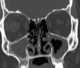

Nasal cavity lesion

Nasal septum perforation

Nasopharyngeal lesion

Paranasal sinus mass

Paranasal sinus opacification

Sinonasal lesion

Sinus disease with bone destruction

Unilateral nasal cavity mass